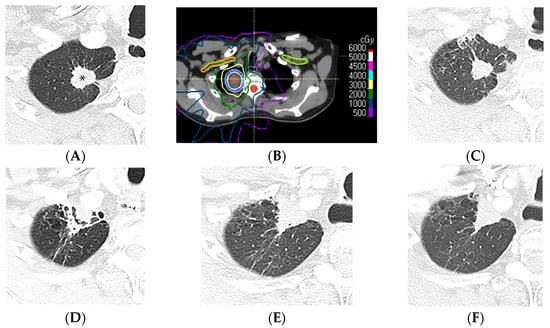

4.1. Modified Conventional Pattern

4.2. Mass-like Pattern

4.3. Scar-like Pattern

4.4. Organizing Pneumonia

5. Imaging Modalities and Radiomics

5.2. Computed Tomography

5.3. Positron Emission Tomography/Computed Tomography